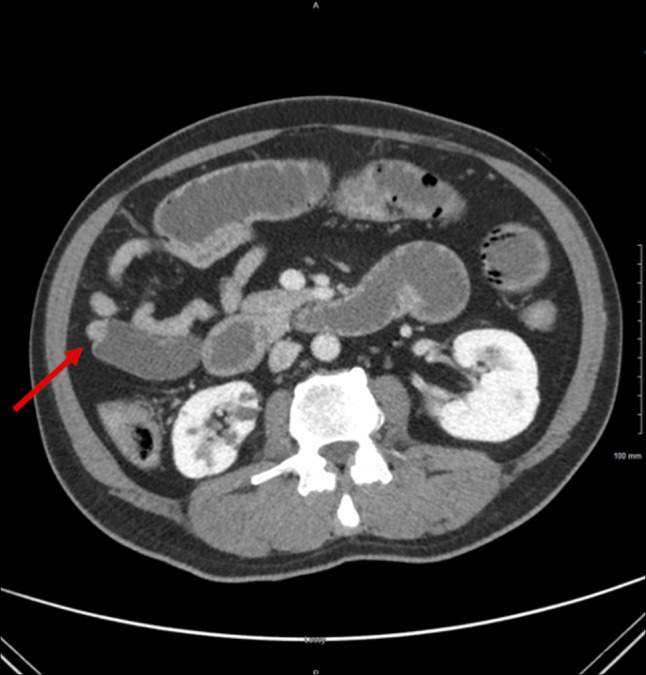

如果处理不当,结肠镜检查前的肠道准备会导致严重的并发症。我们报告一个53岁的男性病例,由于用药错误,将聚乙二醇与车前草混淆,导致小肠梗阻和肠肺病。虽然车前草通常是安全的,但如果大量摄入会引起梗阻。虽然患者对保守治疗反应良好,但本病例显示了泻药滥用的严重并发症。明确的患者教育对于结肠镜检查前肠道准备的安全性和有效性至关重要。

Bowel preparation for colonoscopy can lead to severe complications if mismanaged. We present a case of a 53-year-old man who developed small bowel obstruction and pneumatosis intestinalis due to a medication error, confusing polyethylene glycol with psyllium. While generally safe, psyllium is known to cause obstruction if ingested in large quantities. While the patient responded well to conservative treatment, this case demonstrates a serious complication of laxative misuse. Clear patient education is essential for the safety and efficacy of bowel preparation before colonoscopy.